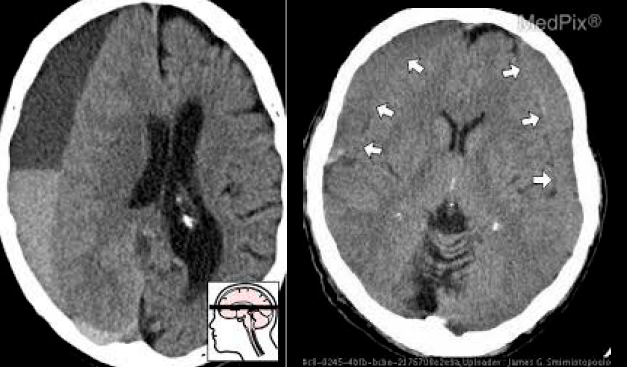

Q

TCE

¿Qué tipo de hematoma es este?

A

Subdural

23

Subaracnoideo (hemorragia)